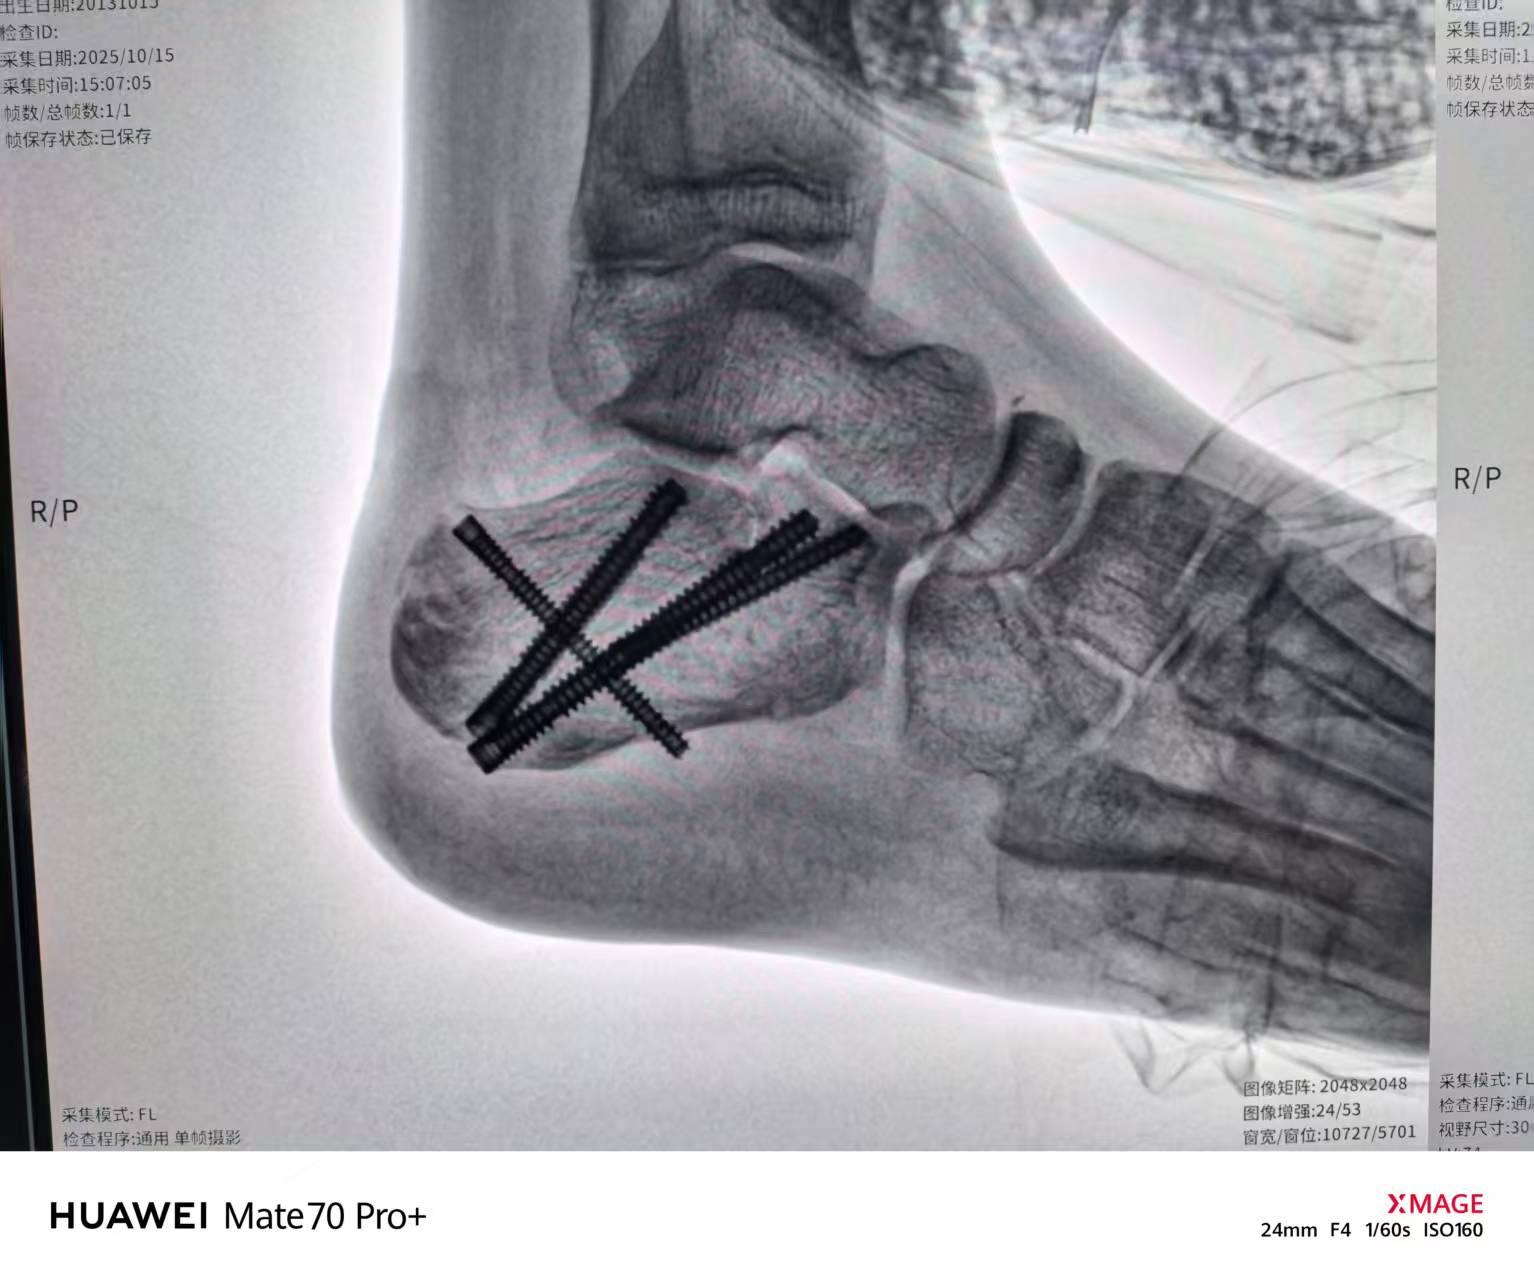

10月15日,手术在严安副主任医师主刀下展开。在骨科手术机器人的精准导航下,医生仿佛拥有了“透视眼”和“稳定手”。通过屏幕上三维模型的实时引导,手术器械沿着预设的最优路径,经皮直达骨折深处。医生巧妙地利用牵引和撬拨技术,将破碎的跟骨关节面一一归位,随后在机器人引导下,将数枚空心螺钉精准植入,完美固定。手术仅留下微小创口,出血量得到有效控制。